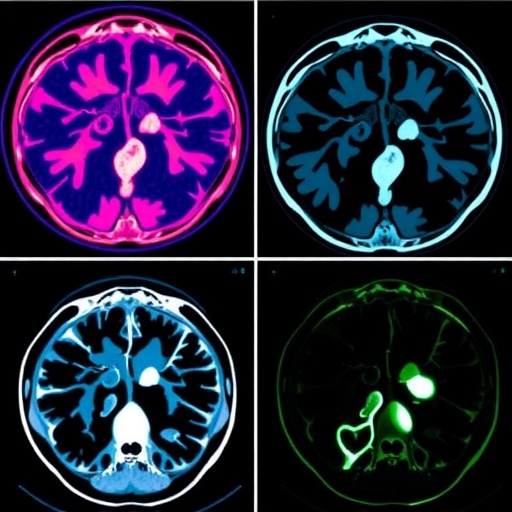

In the evolving landscape of cancer treatment, the utilization of advanced radiation therapy systems has markedly improved the precision and effectiveness of tumor targeting. Among these systems, CyberKnife radiosurgery stands out, offering a refined approach to delivering high doses of radiation with minimal damage to surrounding healthy tissues. A recent study conducted by Tian and colleagues explores the dosimetric outcomes between two distinct collimation techniques—multi-leaf and circular collimators—in the context of CyberKnife treatments. This comparative analysis spans various lesion types, specifically targeting intracranial, hepatic, and prostatic tumors, with a focus on differing tumor sizes and complexities.

Moreover, as the field of medical imaging continues to develop, future research could expand upon this work by incorporating sophisticated imaging modalities to further optimize treatment planning. Advanced imaging techniques such as MRI and PET scans can provide vital insights into tumor metabolism and microenvironment, potentially leading to more personalized treatment regimens. The integration of imaging with treatment planning may unlock new avenues for enhancing the precision of radiosurgery across various clinical contexts.